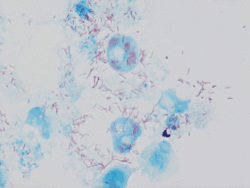

| Rickettsia conorii observed in Vero cells (red rods; magnification ×1,000)[1] | |